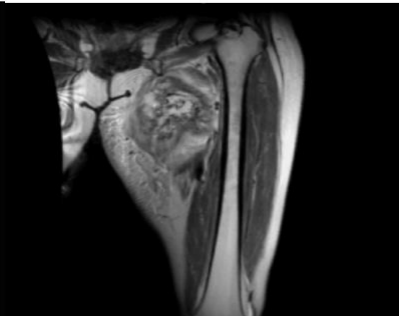

Magnetic resonance imaging (MRI) revealed a 4.7x7.2x9 cm irregular soft tissue mass in the left medial proximal thigh involving the adductor magnus muscle. The mass demonstrated intermediate and heterogeneous T2 signal intensity with an irregular peripheral T2 dark signal rim and intermediate T1 signal intensity. Additionally, the MRI showed extensive surrounding muscle and subcutaneous edema with a branch of the deep femoral artery coursing through the mass. Gadolinium-enhanced images revealed multilocular cystic areas surrounded by intense heterogeneous enhancement of the solid components. The mass demonstrated features concerning for malignancy [Figure 1, 2, 3, 4]. A fluorodeoxyglucose (F-18 FDG) PET scan demonstrated mildly hypermetabolic lymph nodes in the left inguinal region (suspected reactive) and a few small inflammatory nodules without FDG uptake in both lungs, but no evidence of distant metastasis [Figure 5].

FIGURE 2: Axial T1-weighted fat-saturated gadolinium-enhanced image Multilocular cystic areas in central part of lesion surrounded by intense heterogeneous enhancement of the solid elements

FIGURE 4: Coronal T2-weighted MR image Mass in adductor compartment of thigh with intermediate and heterogeneous signals